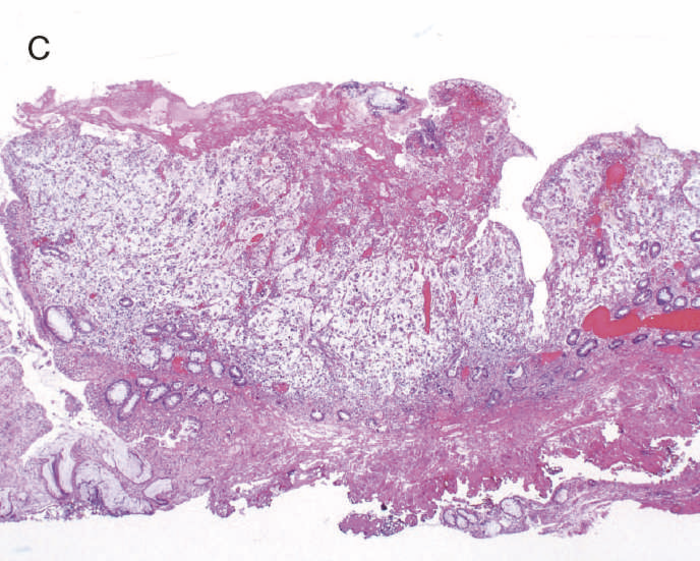

通常の散発性進行大腸癌の多くは潰瘍限局型(2型)であるが,UC関連進行大腸癌は潰瘍浸潤型(3型),びまん浸潤型(4型)や分類不能型(5型)が多いとされる(図7)。初期病変であるdysplasiaの肉眼形態に関しては,混合型を含む約70%の症例が何らかの隆起成分を有することが報告されている1,2)。ただ同じ隆起といっても,UC関連大腸腫瘍の多くは境界不明瞭な丈の低い顆粒状・結節状・不整扁平隆起を呈する一方で,散発性腫瘍は有茎性もしくは亜有茎性病変,境界や立ち上がりが明瞭な病変であることが多く,詳細な肉眼形態の観察は両者の鑑別に重要である。二番目に多い肉眼形態は平坦型であり,全体の約30%を占める1,2)。散発性大腸腫瘍の平坦型は極めて頻度が低いことから,平坦型成分の存在もdysplasiaの特徴といえる(図8)。

- 内腔狭窄を伴った5型の腫瘍(矢印)を認める。

- 組織学的には,粘液癌あるいは低分化腺癌が壁内に浸潤している像を認める。

図8 Dysplasiaの代表的な肉眼像(平坦型)

- 直腸部の赤色点線部より肛門側(左側)に拡がるdysplasia(平坦型)を認める。

- 同平坦部では組織学的に高分化管状腺癌(粘膜内癌)を認めた。